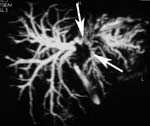

Diagnosis of Klatskin tumors was a domain of ERCP, which may show of bile duct involvement and histologic proof. However, ERCP demonstration of bile duct anatomy is often incomplete due to incomplete ductal filling. MR imaging and helical CT are useful in diagnosis and staging of Klatskin tumors. MRCP in conjunction with contrast-enhanced MRI and MRA allows assessment of tumor size, bile duct involvement (Fig. 2), and vascular infiltration, which is crucial for assessment of resectability. Contrast-enhanced thin-section helical CT may show Klatskin tumors with a sensitivity of up to 100%. Tumors are better seen on arterial-dominant than on portal venous phase scans (sensitivity 100% vs. 86%). However, single-slice helical CT is still inaccurate for assessing resectability (accuracy, 60%), because proximal tumor extension is underestimated. Preliminary experience with multi-slice CT indicates that tumor extension may be better displayed due to 3D-imaging capabilities. Curved planar reconstructions along the main, right, and left portal vein and along the intrahepatic bile ducts show the extent of tumor involvement more precisely. In contrast to “conventional” axial images, they reveal a “pseudosurgical” view of the tumor growth pattern.

[Увеличить]

Fig. 2. MRCP. Klatskin tumor.